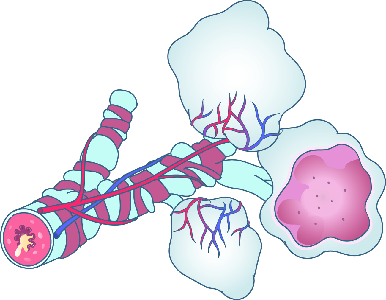

Detailreiche Fotografien aus der medizinischen Praxis ergänzen die Texte; moderne, genaue,

wissenschaftliche Zeichnungen geben Einblick in die Anatomie und die Funktion der Lunge und

anderer Organe.